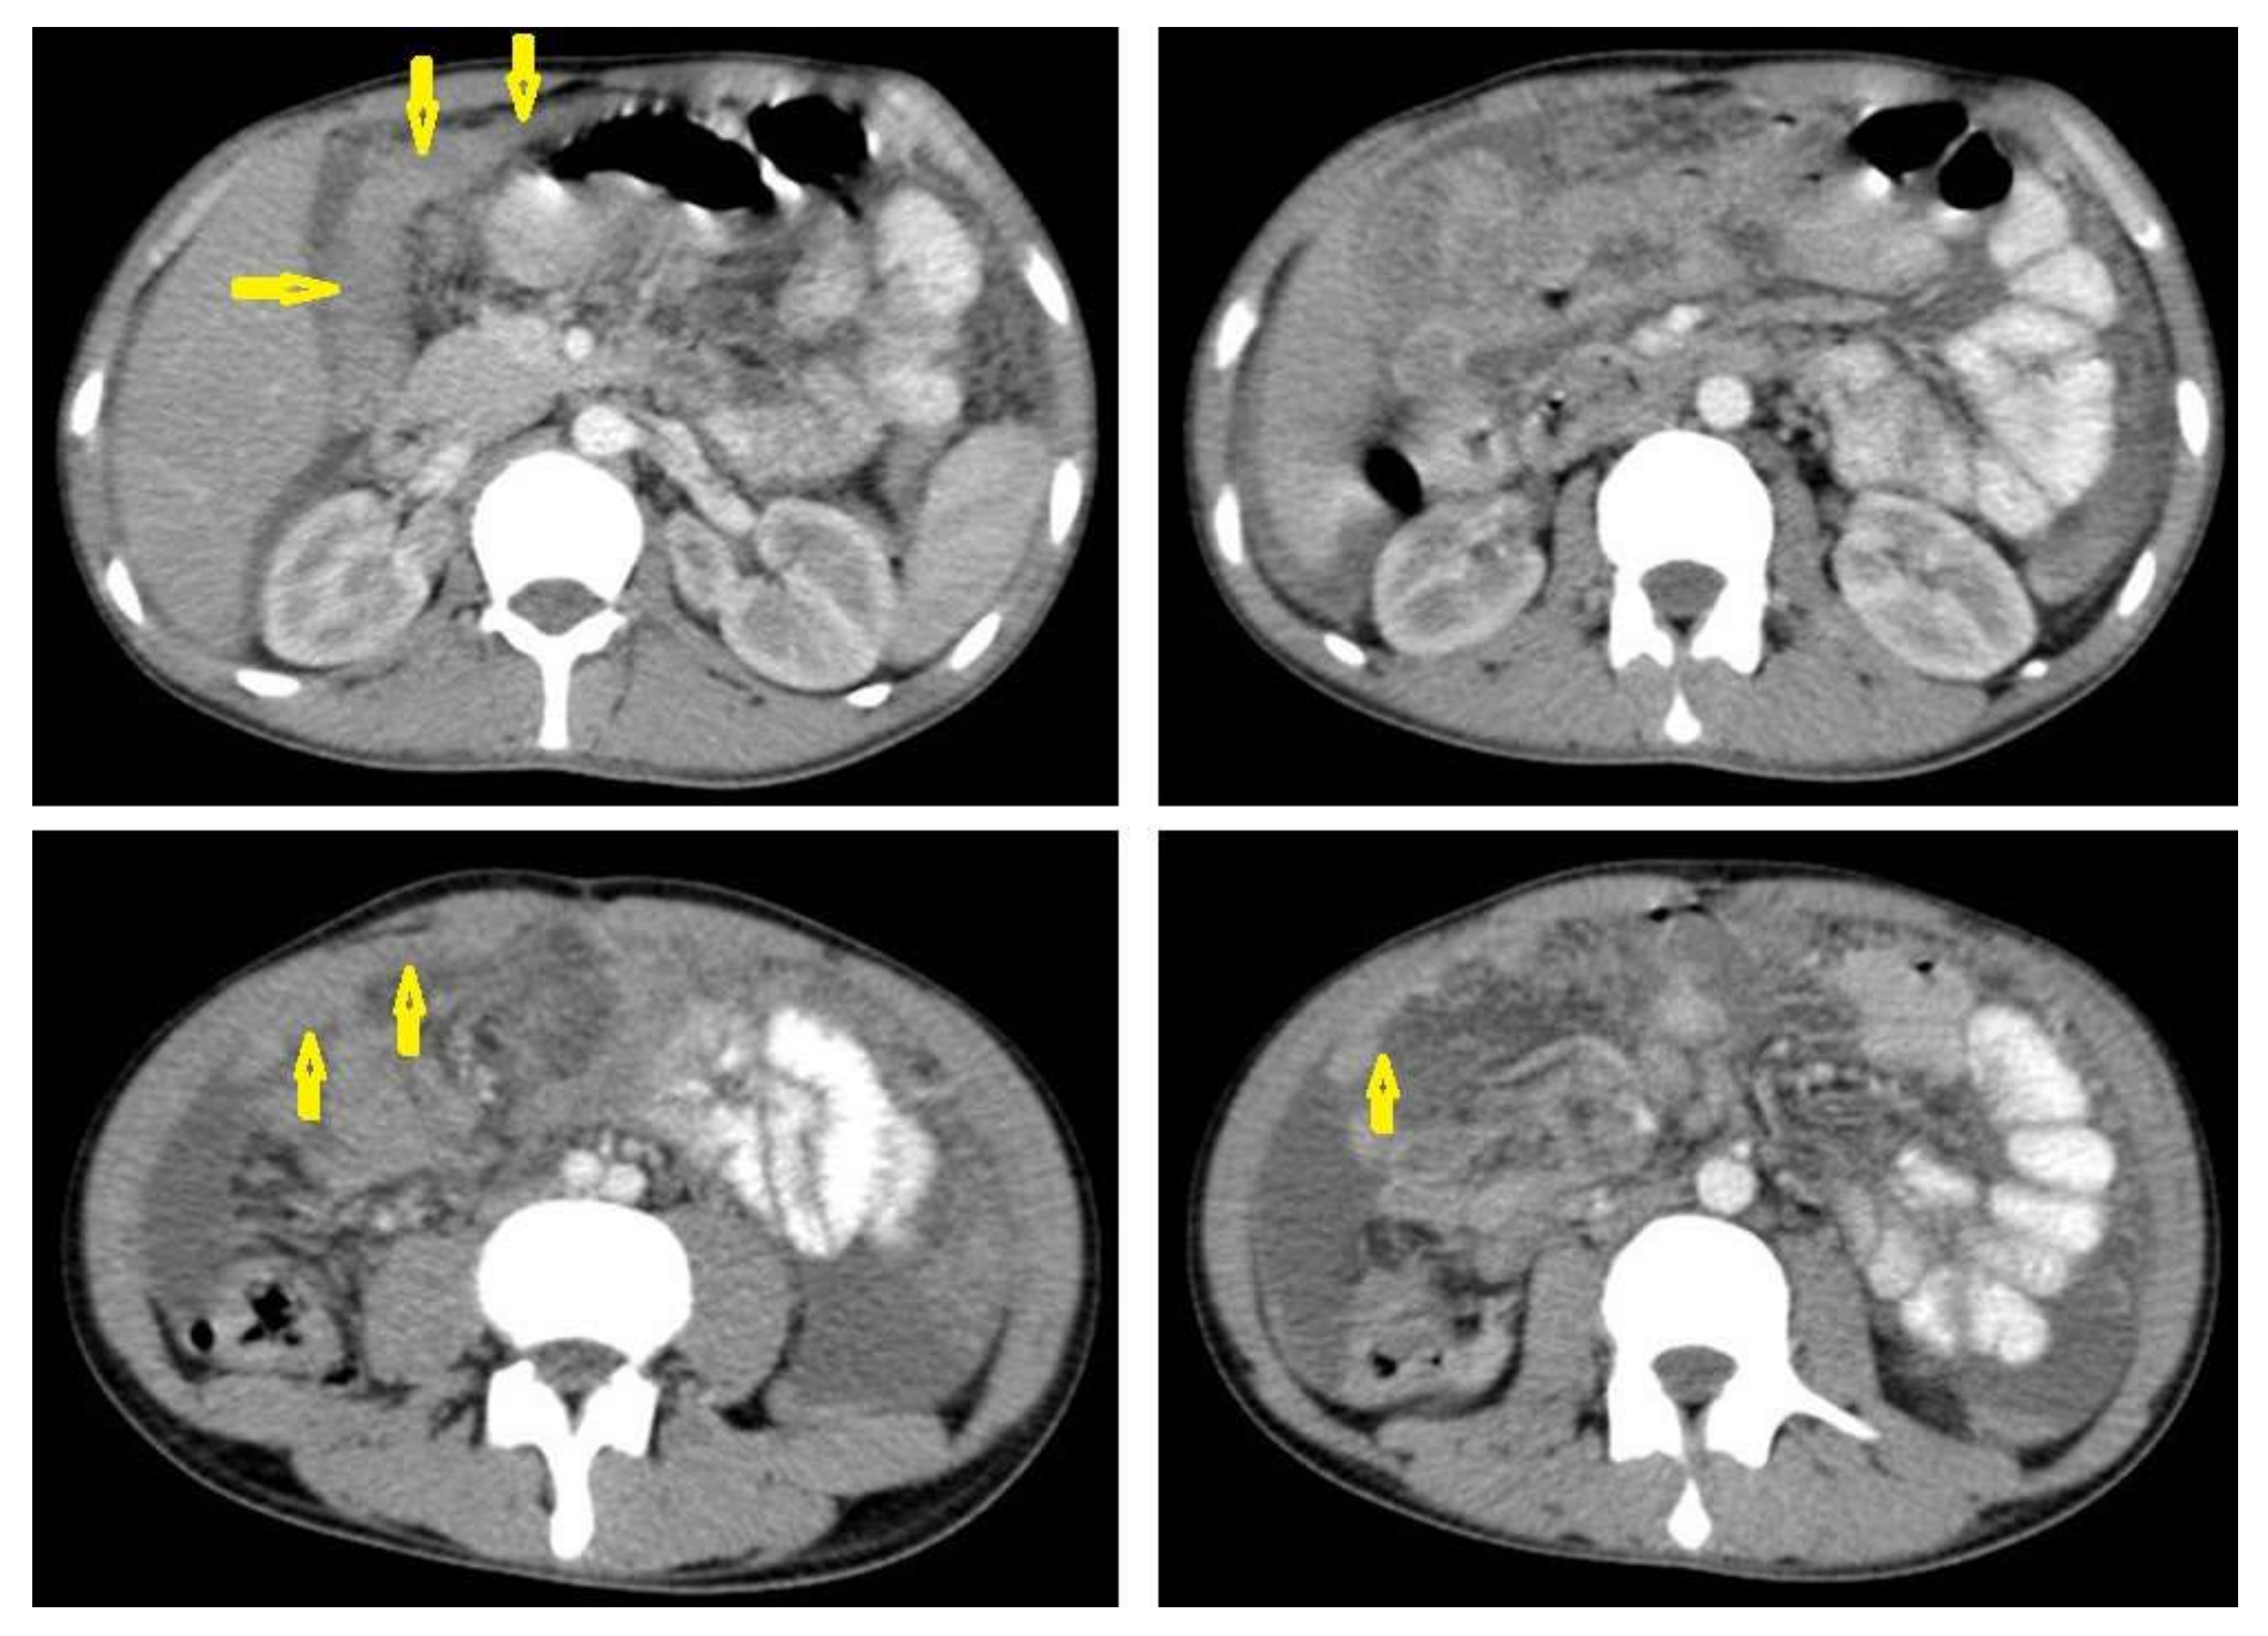

• Tuberculous peritonitis is the most common clinical presentation of abdominal TB. It involves the peritoneal cavity, mesentrium, and omentum. Peritonitis is believed to be originated from hematogenous spread or secondary to LN rupture, gastrointestinal dissemination, or fallopian-tube involvement [46,47]. Tuberculous peritonitis has three radiological patterns:

• Wet peritonitis (Figure 21) is the most common type that is characterized by free or loculated ascites with or without peritoneal thickening [46,47].

• Fibrotic peritonitis (Figure 22) is characterized by remarkable omental and mesenteric thickening forming cake-like masses with bowel loops enlargement and matting that can be seen by CT or ultrasound. [46,47].

Radiological features of tuberculous peritonitis can mimic nontuberculous infectious peritonitis, peritoneal carcinomatosis, peritoneal pseudomyxoma, and mesothelioma [46,47].

Figure 21. Wet peritonitis in a 16-year-old man with cachexia and loss of appetite. Selected axial abdominal images show marked relatively dense ascites and gross thickened omentum with faint enhancement of peritoneal reflections (long arrows) with multiple enlarged mesenteric and upper paraortic conglomerated lymph nodes (short arrows) with slight homogeneous enhancement.

Figure 22. Fibrotic peritonitis in a 20-year-old man with fatigue, abdominal distension, and loss of appetite. Selected axial images of abdominal CT show remarkable omental thickening, forming cake-like masses (arrows) with faint enhancement and mild smooth thickening of peritoneal reflections associated with mild-to-moderate dense ascites and several low-attenuation mesenteric lymph nodes that are challenging to be distinguished from small bowel loops.